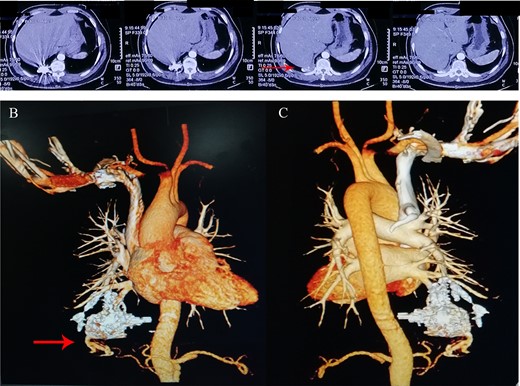

His vital signs were within normal range and oxygen saturation was 98%. But we observed that he had clubbed fingers. Lung auscultation, cardiac examination and brain MRI were unremarkable. The transcranial doppler indicated the presence of right–left shunt. On CT and 3D reconstruction, a dilated and tortuous vessel structure and many coils in the right lower lobe were found (Fig. 2). The patient had no relevant HHT history or family history. The diagnosis was considered as idiopathic recurrent PAVMs and secondary TIA resulting from paradoxical embolization. Then, the patient was transferred to the department of thoracic surgery. A large number of malformed vessels and embolic coils were distributed throughout the right lower lobe, so it was difficult to complete resection only using video-assisted thoracoscopic lobectomy. After thorough discussion, we decided to excise the right lower lobe by Da Vinci robotic-assisted thoracoscopic surgery to completely solve PAVMs, and meanwhile, we could remove the steel ring of previous embolization, so as to avoid complications such as ectopic embolization.

(A) A round density and local artifacts were observed in the lower lobe of the right lung on pre-operative computerized tomography; (B) anterior and (C) posterior 3D reconstruction showed a dilated and tortuous vessel structure in the right lower lobe.